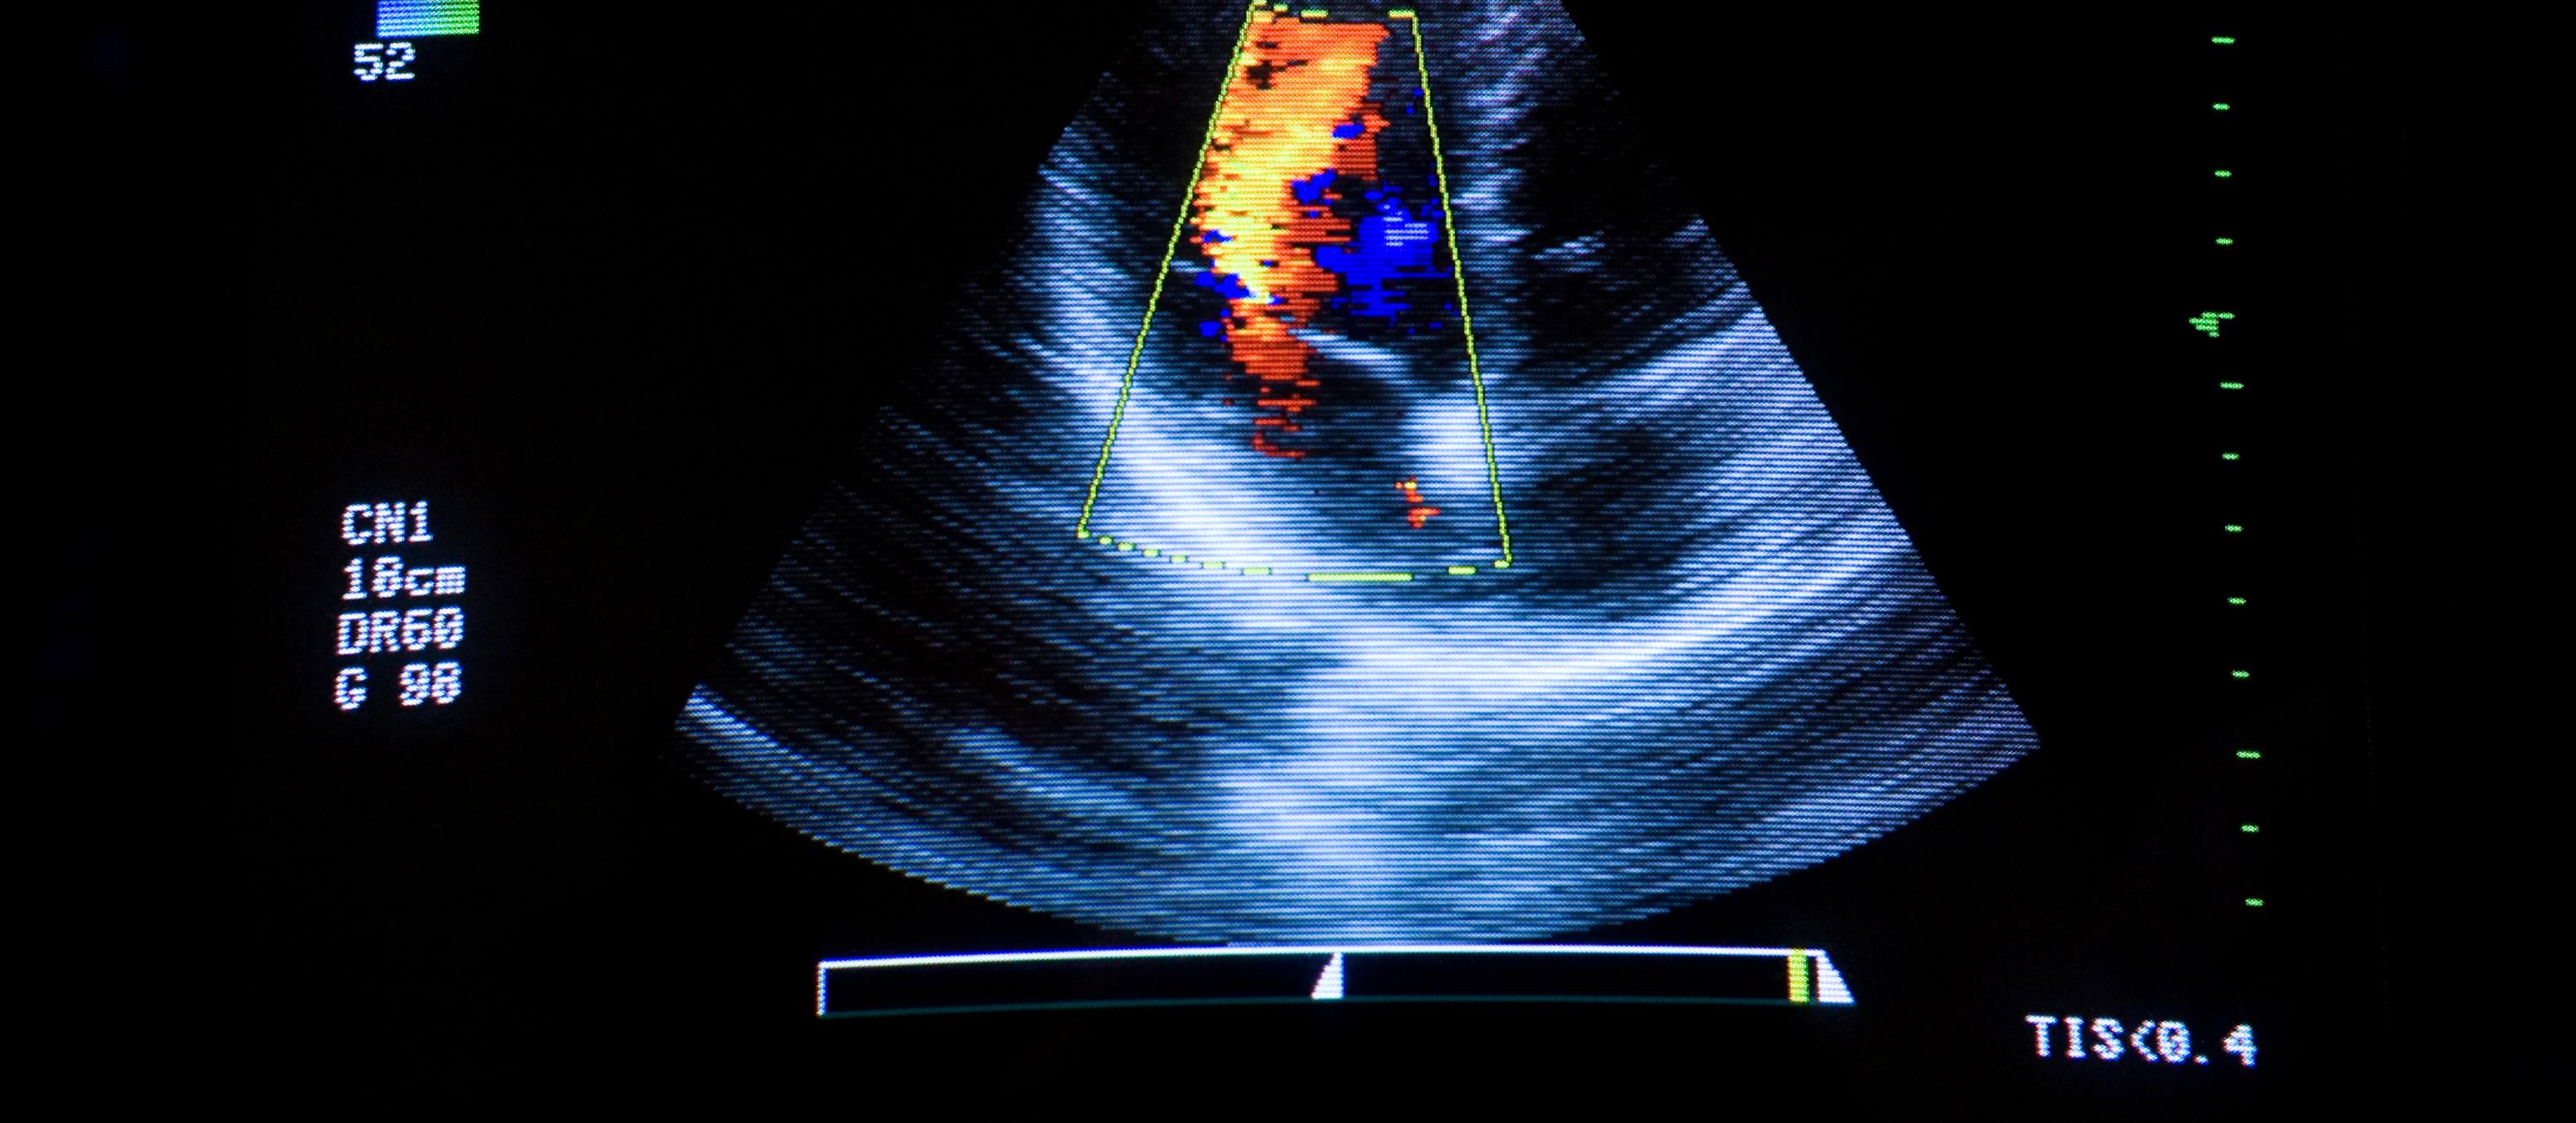

Ultrasound is perhaps the most used imaging modality at health care facilities in the United States and its popularity continues to grow. ICE Magazine reached out to imaging leaders to find out more about ultrasound in this month’s Director’s Circle article. Leaders sharing their insights are:

FUJIFILM Healthcare Americas Corporation’s ARIETTA 750 DeepInsight, a premium diagnostic ultrasound solution that uses Fujifilm’s DeepInsight technologies to increase image clarity and reproducibility, even for the most challenging views. DeepInsight uses cognitive technology algorithms to distinguish between echo signals and electrical noise, selectively removing noise that can obscure tissue signal, while still retaining important acoustic speckle signals. This results in high-quality images, even from deep regions of the body, to support more accurate ultrasound examinations. The system’s software suite is designed to solve common workflow challenges by automating common operations such as Doppler gate placement. The system’s eFocusing Plus uses a non-traditional transmit/receive technique to eliminate focal zones, shorten exam times and uniformly focus at all depths.

The RS85 Prestige ultrasound system offers novel diagnostic features and advanced intelligence technologies to assist sonographers and other health care professionals to diagnose with confidence and ease. Designed for scanning performance, the system delivers consistent image clarity, depth of penetration and sensitivity to perfusion of blood flow. At the core of the image quality is Crystal Architecture, which combines advanced beamforming (CrystalBeam), sophisticated image processing (CrystalPure) and advanced S-Vue transducers to produce clear, uniform, high-resolution images. The RS85 Prestige is empowering ultrasound professionals with diagnostic confidence on even the most challenging of patients.

SIEMENS HEALTHINEERS ACUSON MapleUltrasound System

Siemens Healthineers ACUSON Maple is a powerful, versatile and affordable ultrasound system that enables rapid diagnosis and assessment in all clinical settings. Artificial intelligence (AI)-powered features optimize everyday clinical performance for users of all skill levels. Powered by ACUSON technology from the company’s established portfolio, the ACUSON Maple is designed for the clinician who needs a workhorse ultrasound system that supports a diverse range of ultrasound use cases. Lightweight, portable, and battery-powered, the ACUSON Maple is ideal for emerging markets, small hospitals, outpatient centers, private practices and urgent care centers. Designed for versatility, the ACUSON Maple supports 15 transducers and has 25 advanced features that enhance usability and streamline workflow. An integrated battery enables up to 75 minutes of unplugged system scanning. The system’s suite of AI-powered tools empowers clinicians to improve efficiency by increasing consistency in repetitive tasks. For obstetrics and gynecology (OB/ GYN) imaging, the Auto OB feature leverages machine learning to automatically calculate the fetus’s age and weight. For cardiac imaging, the eSie Measure feature uses machine learning to automatically perform cardiac measurements during a routine echocardiography exam. The ultrasound system is cleared by the U.S. Food and Drug Administration, CE marked in the European Union, and is available globally.

PHILIPS 5000 Series 5